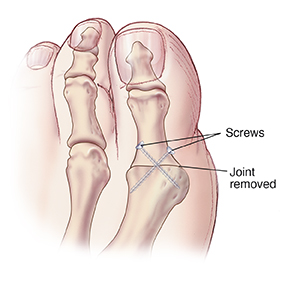

Fusion

In fusion, the cartilage and some bone on both sides of the joint are removed. Then, the big toe and metatarsal bones are held together with staples, screws, or a plate and screws. Your foot may be placed in a cast, shoe, or boot. While you heal, you will be asked not to bear weight on this foot. You may also need crutches for several weeks. Because the joint has been removed, your toe will be less flexible.